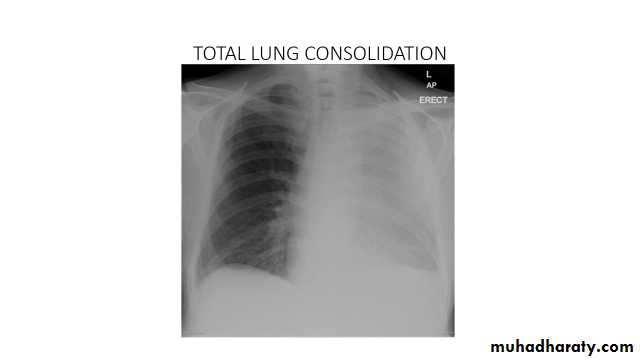

Total lung collapse

chest X-ray